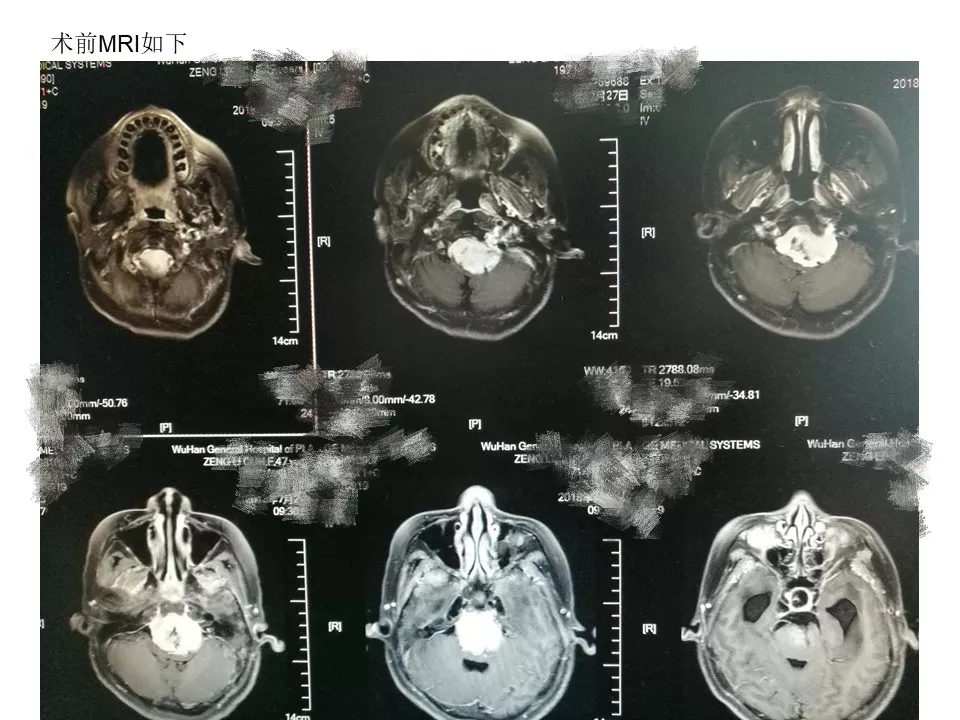

今天为大家分享的是《贝朗时间》第三十八期,由中国人民解放军武汉总医院神经外科副主任姚国杰教授带来的:远外侧入路全斜坡巨大脑膜瘤显微手术1例,欢迎阅读、分享!

远外侧入路全斜坡巨大脑膜瘤显微手术1例